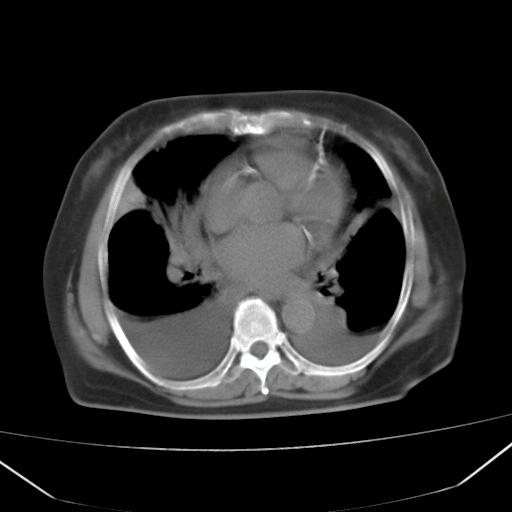

以下是引用liuyue在2008-4-19 22:25:00的发言:[br]先考虑:1.心衰伴肺水肿、双侧胸腔积液、叶间积液、双下肺不完全性肺不张; [br] 2.冠状动脉粥样硬化。

以下是引用lijuanln在2008-4-19 23:05:00的发言:[br]两侧胸腔积液,肺水肿[br]心包积液[br]提示心衰

以下是引用jiangjing在2008-4-20 10:43:00的发言:[br]结合病史支持 冠心病[冠状动脉钙化],心功能不全,肺淤血、肺水肿,双侧胸腔与斜裂积液